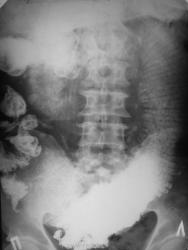

При исследовании ЖКТ -эктазия желудка и первых петель тонкой кишки, далее контрастное вещество не пошло.

Снимки через 24 и 36 часов

Надо подумать о препятствии в илео-цекальной области.

Спайка в илеоцекальной области, сдавливающая тонкую кишку косо-поперек.

Это зктазированы первые 50 см "тощей" кишки!

Так не против же "тощей", но проекционно препятсвие где?

Давит сегодняшняя "глистная инвазия", ну прямо давит, да еще и "крапочки" какие-то на левом снимке справа на уровне Л2, Л3.

Проходимость мизерная... практически полный стеноз...

Высокая тоно-кишечная вероятно обутрационная непроходимость. Причин может быть много. Например безоар,желчный камень,клубок аскарид,опухоль, штранг в сальнике,аномалии развития и тд.

На операции редкая локализация аденокарциномы тощей кишки, 50-60 см от связки Трейца, полное сужение провета. Резекция фрагмента кишки. Видимых метастазов не было, отдаленный результат не знаю...